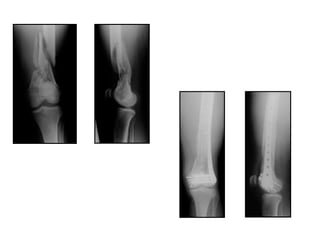

Fracturas femur distal